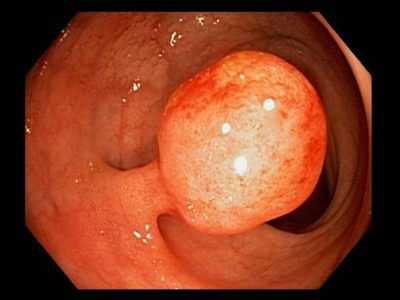

- По форме:

- на толстой или тонкой ножке;

- ровные и гладкие;

- с неровной и бугристой поверхностью, такие полипы похожи на гроздь винограда [7][10] .

Полипы следует отличать от геморроя. Различие состоит в структуре геморроидальных узлов и полипов — геморроидальная ткань имеет сосудистую природу, а полипы состоят из фиброзной ткани. Полипы белесоватого цвета, плотные и грубые, чаще всего на тонкой ножке с булавовидной головкой.